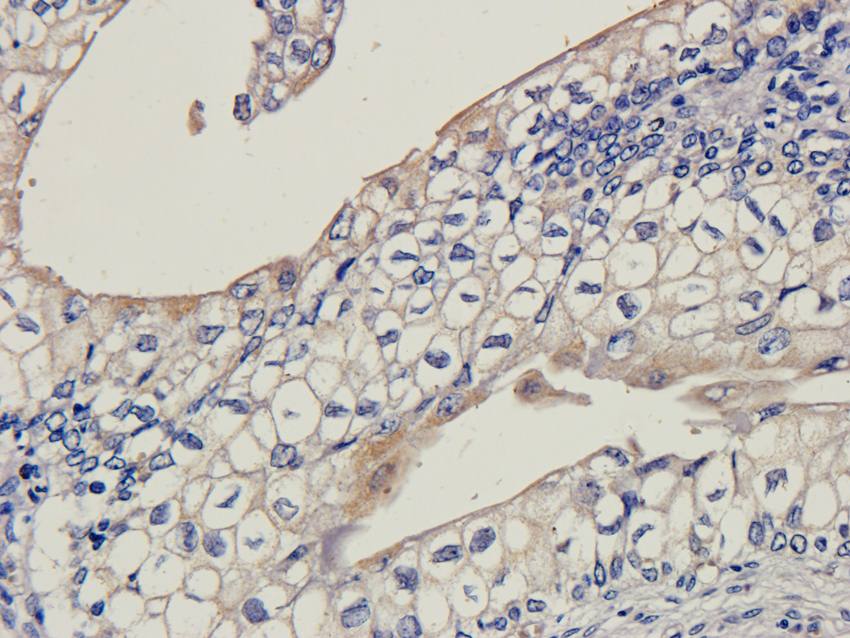

应用稀释比例:IF/ICC: 1:50-400, WB: 1:200-1000, IHC-P: 1:50-400